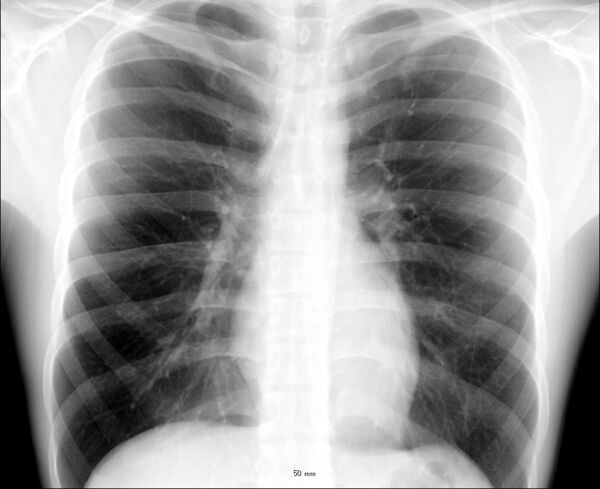

Рентгеноанатомия органов грудной клетки

При изучении рентгеноанатомии органов грудной клетки обращают внимание на рентгеновскую структуру видимых костей и мягких тканей грудной клетки; форму и прозрачность для рентгеновских лучей областей, на которые проецируется лёгочная ткань (так называемых «лёгочных полей»), а также их структуру, сформированную тенями сосудов лёгких («лёгочный рисунок»); расположение и структурность корней лёгких; положение, форму куполов диафрагмы и синусов плевральных полостей; форму и размеры тени средостения (в том числе сердца).

Рёбра являются ориентиром для оценки расположения других структур грудной клетки. При обзорной рентгенографии лёгких в прямой проекции в норме визуализируются передние отрезки верхних пяти или шести пар рёбер. Рёберный хрящ на рентгенограмме не виден (при отсутствии его обызвествления), в связи с чем изображение грудинных концов рёбер прерывается на некотором расстоянии от грудины. Тени передних отрезков рёбер направляются кнаружи и кверху от срединной линии; задних отрезков — кнаружи и книзу. Помимо изображения рёбер, на рентгенограммах грудной клетки визуализируются тени ключиц и лопаток (последние при правильно выполненном снимке не накладываются на лёгочные поля). На рентгенограмме, выполненной с оптимальными условиями, также различимы тела первых трёх грудных позвонков. Среди теней мягких тканей, покрывающих грудную клетку, различимы изображения грудино-ключично-сосцевидных мышц (в проекции медиальных отделов верхушек лёгких); грудных мышц (в верхне-латеральных отделах лёгочных полей); молочных желёз и сосков. Иногда над ключицами можно увидеть тонкие тени кожных складок.[3][4]

Лёгкие на рентгенограмме образуют лёгочные поля, располагающиеся по обе стороны от интенсивной тени средостения. Правое лёгочное поле короче и шире левого. В лёгочных полях различают верхушки (зоны выше ключиц), верхние отделы — от верхушек до передних отрезков вторых рёбер, средние отделы — между вторыми и четвёртыми парами рёбер, и нижние отделы — от четвёртых рёбер до диафрагмы. Лёгочные поля в норме очень светлые (тёмные на негативе) из-за высокой рентгенопроницаемости заполненной воздухом лёгочной ткани. Структура лёгочных полей называется лёгочным рисунком, анатомическим субстратом которого являются лёгочные сосуды и, в малой степени, лёгочный интерстиций. Лёгочный рисунок визуализируется в виде переплетения сосудистых теней тяжистого, округлого и овального вида, более интенсивных в местах их пересечений. В направлении от корней лёгких к периферии рисунок лёгочных сосудов становится беднее и совсем не визуализируется на расстоянии 1—1,5 см от края лёгочных полей. Лёгочный рисунок наиболее густой в нижних отделах лёгочных полей, обедняясь к верхушкам. Тени бронхов на рентгенограмме визуализируется в виде двойных полосок или колец с просветлением внутри.[3][4]

Тень корней лёгких определяется парамедиастинально на уровне передних отрезков II—IV рёбер, левый корень располагается несколько выше правого и частично скрыт тенью средостения. Ведущим анатомическим субстратом в формировании тени корней лёгких являются лёгочные артерии и бронхи, в меньшей степени — лёгочные вены и другие структуры. В норме корни лёгких имеют неоднородное изображение, представляя собой структурированную совокупность элементов различной плотности. В корнях лёгких различают головку, тело и хвост. Правый корень визуализируется на всём протяжении в виде лентовидной, суживающейся книзу изогнутой тени средней интенсивности, отделённой от тени сердца промежуточным и нижнедолевым бронхами. К периферии от корней лёгких отходят лёгочные сосуды, причём артериальные ветви имеют более вертикальное направление, венозные — более горизонтальное. Ширина корня лёгкого соответствует ширине его основного артериального ствола; в норме она равна ширине бронха, отделяющего корень от средостения, и не превышает 1,5 см.[3][4]

Нижние границы лёгочных полей образованы тенью диафрагмы. Куполы диафрагмы имеют вид изогнутых кверху дуг, направляющейся от боковых отделов грудной стенки к средостению. Правый купол диафрагмы при глубоком вдохе располагается на уровне передних отрезков V—VI рёбер, левый — на одно ребро ниже. В боковых отделах куполы диафрагмы образуют острые углы с рёбрами, формируя рёберно-диафрагмальные синусы. В медиальных отделах куполы диафрагмы, пересекаясь с тенью средостения, формируют менее глубокие кардио-диафрагмальные синусы, форма которых варьирует. Правый купол диафрагмы снизу не дифференцируется от тени печени, под левым куполом диафрагмы обычно видны единичные просветления, соответствующие скоплениям газа в желудке и селезёночном углу ободочной кишки.[3][4]

Сердечно-сосудистая тень занимает центральное положение на рентгенограмме органов грудной клетки. На рентгенограмме в прямой проекции её контуры в норме формируют две дуги справа и четыре — слева. Нижняя дуга правого контура образована правым предсердием, верхняя, более медиальная — восходящей частью аорты и верхней полой веной. Первая (верхняя) левая дуга образована дугой и начальным отделом нисходящей аорты, вторая — лёгочным стволом, третья — ушком левого предсердия, четвёртая — левым желудочком. В области второй и третьей дуг контур тени средостения вогнут и носит на этом уровне название «талия сердца»; эта зона является границей между сердцем и связанными с ним сосудами.[5]